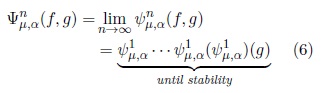

Let us take one of these operators defined as follows in terms of connected viscous openings and closings[2]:

For fixed parameters λ1, λ2, with λ1≤ λ2 ≤ μ,

From last equation and for a family {λi}, with λj≤ λk if j < k, the following VASF is defined[2]:

with the condition λn ≤ μ.

The VASFs will be used to segment some regions of interest. The segmentation process consist in flat the maxima and minima iteratively through the viscous opening and closing. At the end with a threshold is posible to recover the flatened zones under study. Fig. 3 illustrates the performance of Nλn,μ. Notice that, the brain has been completely separated.